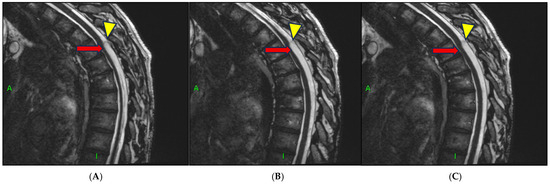

- Chang, H.S.; Nagai, A.; Oya, S.; Matsui, T. Dorsal spinal arachnoid web diagnosed with the quantitative measurement of cerebrospinal fluid flow on magnetic resonance imaging. J. Neurosurg. Spine 2014, 20, 227–233. [Google Scholar] [PubMed]

- Grewal, S.S.; Pirris, S.M.; Vibhute, P.G.; Gupta, V. Identification of arachnoid web with a relatively novel magnetic resonance imaging technique. Spine J. 2015, 15, 554–555. [Google Scholar] [CrossRef] [PubMed]

- Nada, A.; Mahdi, E.; Mahmoud, E.; Cousins, J.; Ahsan, H.; Leiva-Salinas, C. Multi-modality imaging evaluation of the dorsal arachnoid web. Neuroradiol. J. 2020, 33, 508–516. [Google Scholar] [CrossRef]

- Mauer, U.M.; Freude, G.; Danz, B.; Kunz, U. Cardiac-gated phase-contrast magnetic resonance imaging of cerebrospinal fluid flow in the diagnosis of idiopathic syringomyelia. Neurosurgery 2008, 63, 1139–1144. [Google Scholar]